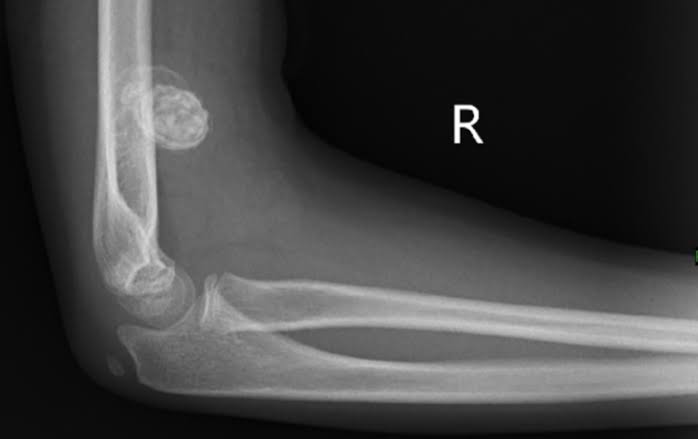

Which of the following is incorrect with respect to image below. A. Most common leukemia in children B. Most common leukemia in Down Syndrome C. Has good prognosis in children, poor in adults D. Boys have better prognosis.